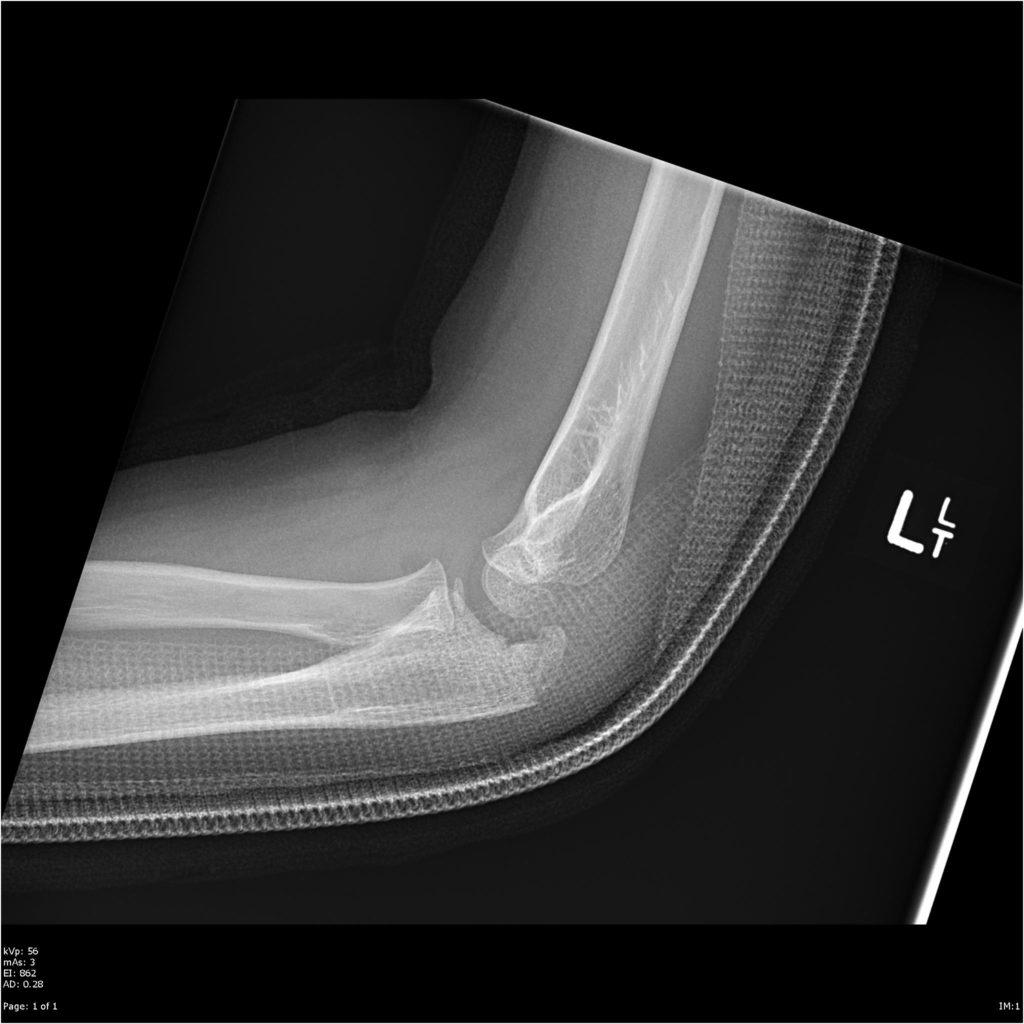

A Plain xray of the left elbow showed cranial displacement of a Left Elbow Olecranon Fracture The pointy tip of your elbow (the olecranon) is part of the ulna — one of the two bones. an olecranon fracture is a break in a part of the ulna bone, which makes up the point of the elbow. an olecranon fracture usually causes sudden, intense pain and can prevent you from moving your elbow. Surgical management. Left Elbow Olecranon Fracture.

Preoperative lateral Xray of the left elbow showing fracture of the Left Elbow Olecranon Fracture Surgical management is the treatment of choice, with specific guidelines for physiotherapy going with it. an olecranon fracture usually causes sudden, intense pain and can prevent you from moving your elbow. Other signs and symptoms of a fracture. if the joint is displaced following the fracture, we’ll need to stabilize it with wires or plates, which are inserted. Left Elbow Olecranon Fracture.